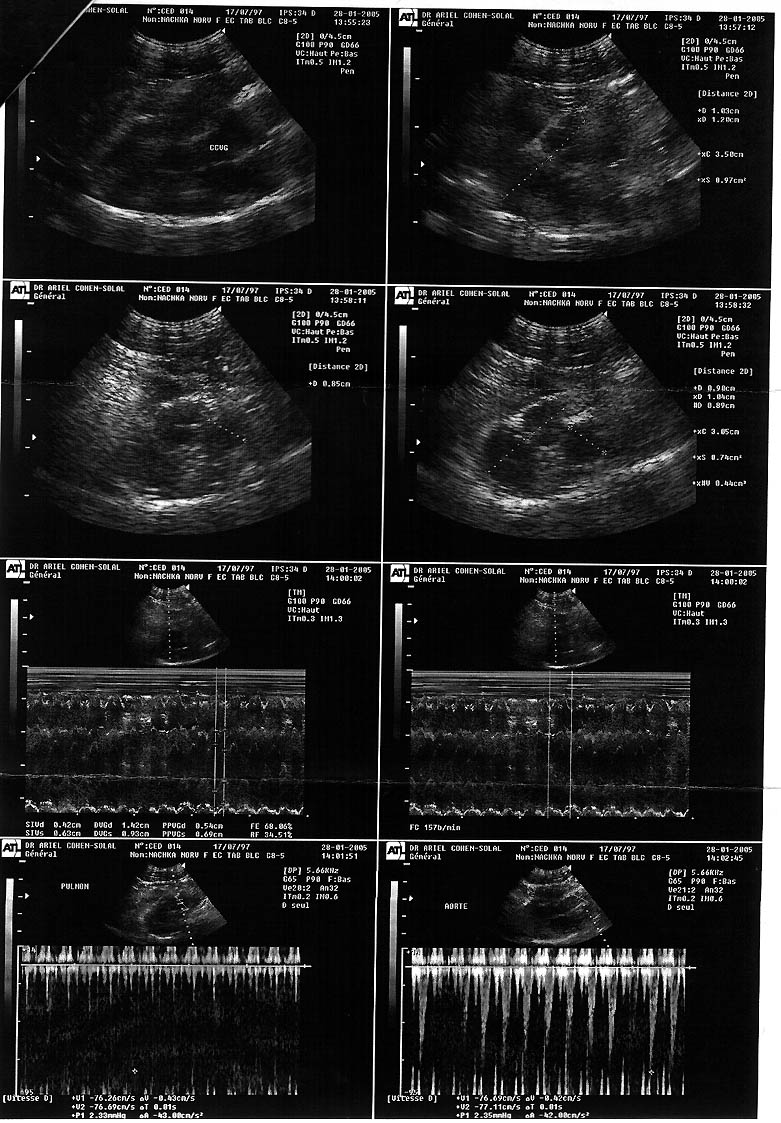

| Nachka du Royaume d'Angmar*F - (F/S) |

David Cayet | 17/07/1997 | first premier |

none aucune |

normal | 7.5 years / ans |